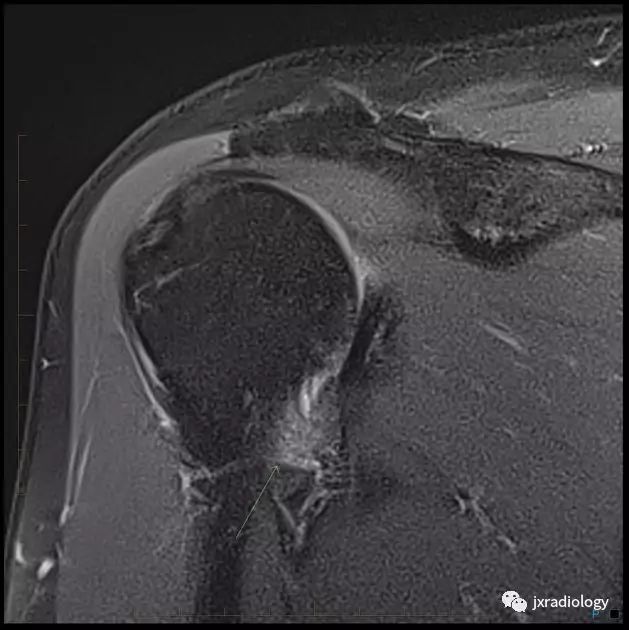

腋囊的增厚和水肿

肩袖间隙异常软组织信号(细箭)

腋囊增厚和水肿(细箭)

• 正常下盂肱韧带测量值<4毫米,在斜冠位上关节囊中间层面显示最好;在粘连性关节囊炎患者中,腋隐窝软组织增厚≥1.3厘米

• 关节囊增厚

• 肩袖间隙异常软组织增厚伴信号异常